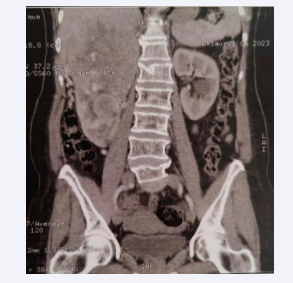

With radiological appearance of mid-renal and upper polar oval tumor mass with heterogeneously enhanced calcifications measuring 135*105*170mm arriving in contact with the Gerota fascia (Figure 1), with renal vena and inferior vena cava thrombosis visible on a Doppler ultrasound.

Right upper renal mid and polar tumor process scanner  131*108*145mm.

Figure 1: Right upper renal mid and polar tumor process scanner 131*108*145mm.